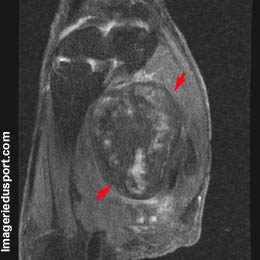

D - IRM de la main, coupe sagittale T1 gado fat-sat : Réhaussement hétérogéne du signal de la masse.

Sarcome de l'eminence thenar.